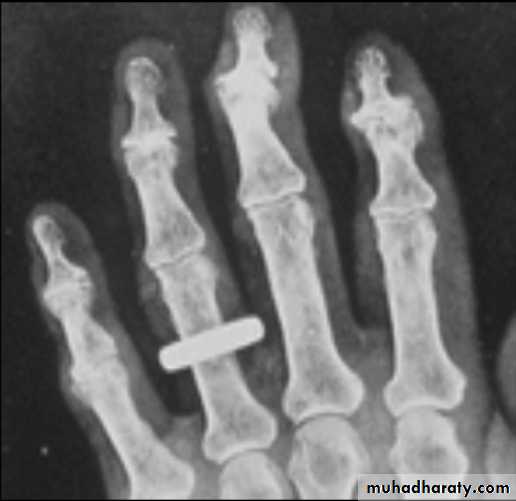

Plain radiographyShow changes of many bone and joint diseases . Radiographs are of diagnostic value in osteoarthritis

(OA), where they demonstrate joint space narrowing

that tends to be focal rather than widespread, as in

inflammatory arthritis. Other features of OA detected on

X-ray include osteophytes, subchondral sclerosis, bone

cysts and calcified loose bodies within the synovium . Radiographs may show erosions and sclerosis of the sacroiliac joints and syndesmophytes in the spine in seronegative spondyloarthritis. In peripheral joints, so-called proliferative erosions, associated with new bone formation and a periosteal reaction, may be observed.

In tophaceous gout, well-defined punched-out erosions may occur .

Calcification of cartilage, tendons and soft tissues or muscle may occur in chondrocalcinosis , calcific periarthritis and connective tissue diseases. Radiographs are of limited value in the diagnosis of rheumatoid arthritis (RA) since features such as erosions, joint space narrowing and periarticular osteoporosis may only be detectable after several months or even years.Early evidence of articular damage in RA is more usually obtained using MRI or ultrasonography.